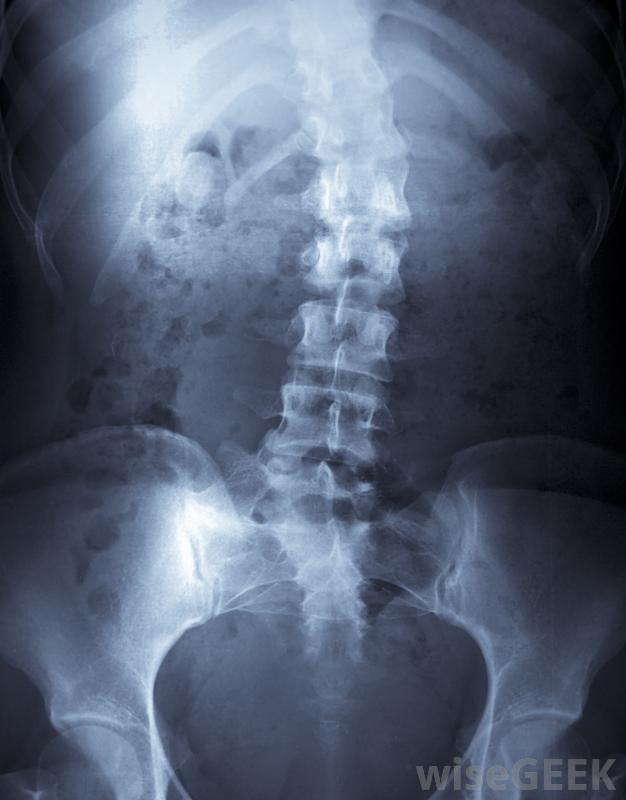

椎間盤突出是一個術語,泛指椎間盤在兩個椎骨之間受壓的異常情況。它也被稱為椎間盤突出、椎間盤膨出、椎間盤壓縮和椎間盤脫出。椎間盤滑脫通常會引起輕微到嚴重的疼痛。這取決于破裂的部位,也會導致四肢麻木和刺痛,嚴重時,椎間盤滑脫會干擾腸道和膀胱功能,造成危及生命的緊急情況。這種情況稱為脊柱側凸是脊柱的一種彎曲,它會對椎間盤產生過大的壓力。脊柱是由一塊又一塊的扁平的骨頭組成的,這些骨頭相互堆疊,具有獨立運動的能力,使背部具有其特有的柔韌性。在椎骨之間,椎間盤是甜甜圈形狀的軟墊,外殼由軟骨制成,海綿狀的凝膠狀填充物可吸收跑步、跳躍或其他劇烈運動產生的沖擊。當椎間盤受到上下椎骨的過大壓力時,外表面腸衣可能會受損,使凝膠填充物泄漏到周圍的體腔中。當這種材料壓迫脊柱神經時,會導致疼痛、感覺喪失和身體其他部位功能喪失滑碟可能是車禍造成的椎間盤有多種損傷。椎間盤滑脫可由嚴重創傷引起,如車禍或運動損傷。脊柱側凸會對椎間盤造成過大的壓力,嚴重的肥胖也會對椎間盤施加超過設計承受能力的壓力。椎間盤退行性疾病是一種正常的衰老過程,導致椎間盤收縮和變脆,使其更容易受傷。椎間盤滑脫會導致背部疼痛椎間盤滑脫或破裂通常由醫生用x光片、CT掃描或MRI掃描來診斷。由于椎間盤是由軟組織構成的,所以在標準的x光片上看不到,醫生可以觀察和測量椎骨之間的間隙,以確定是否需要進行更多的檢查。CT和MRI掃描允許醫生查看軟組織,以確定椎間盤滑脫的確切位置,以及從椎間盤逸出的椎間盤材料的數量和位置MRI掃描可用于診斷椎間盤滑脫。椎間盤滑脫的治療方法因其原因和嚴重程度而異任何治療的目的都是減輕受傷椎間盤的壓力保守的治療方法包括物理治療、按摩、消炎藥物、飲食和運動改變(如果肥胖是主要原因)。脊柱側凸可以用背托進行治療。如果損傷危及生命,或者疼痛不能通過更保守的方法緩解,可能需要手術移除破裂的材料并穩定周圍的椎骨。您應該與醫生討論適合您情況的治療方案。健康的脊柱和椎間盤滑脫或壓縮。